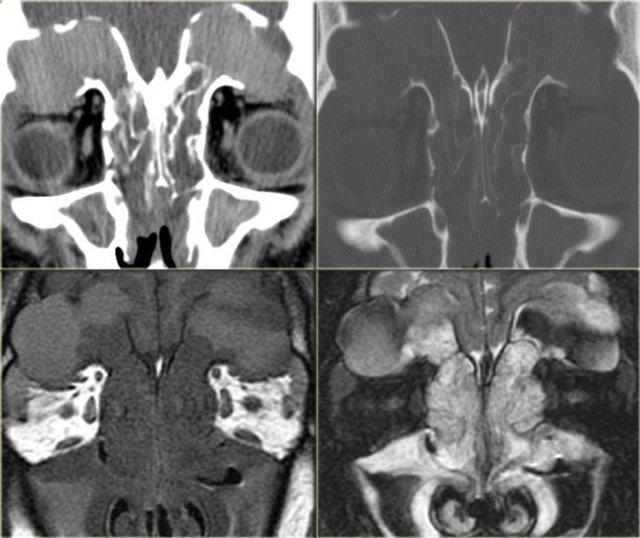

Bên trái là một trường hợp ban đầu được chẩn đoán nhầm là khối u.

Có vật chất tăng tỷ trọng ở xoang sàng sau bên phải, các ngách bướm-sàng hai bên, xoang bướm và có sự xâm lấn vào xương nền sọ (clivus).

Tình trạng tăng tỷ trọng là dấu hiệu tiên lượng tốt, gợi ý một quá trình lành tính.

Đây là ví dụ điển hình của viêm xoang nấm dị ứng.

Bên trái là một ví dụ khác, điển hình hơn, của viêm xoang nấm dị ứng.

Có hình ảnh mờ đục hai bên hốc mũi, thường là dấu hiệu của quá trình viêm hoặc polyp.

Lưu ý hình ảnh phân lớp đồng tâm xen kẽ giữa tăng tỷ trọng và giảm tỷ trọng trong các xoang hàm.

Tình trạng tăng tỷ trọng là do dịch tiết đặc quánh và các thành phần nấm.

Tình trạng giảm tỷ trọng phản ánh các nang, bệnh lý niêm mạc và mô hạt.

Ở vùng xoang sàng, một phần tình trạng tăng tỷ trọng phản ánh viêm màng xương và tân tạo xương dọc theo các vách ngăn.